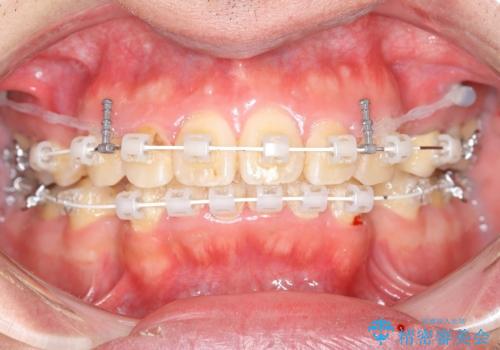

抜歯する事で歯の移動量が大きいことからワイヤー表側矯正装置で治療を行うことになりました。

今回のような歯の移動量が大きい場合、インビザライン治療では歯が傾いてしまう場合があります。

ワイヤー治療では歯の傾きを抑えながら大きい距離の移動が可能で、かみ合わせが深くなるリスクも少ないです。